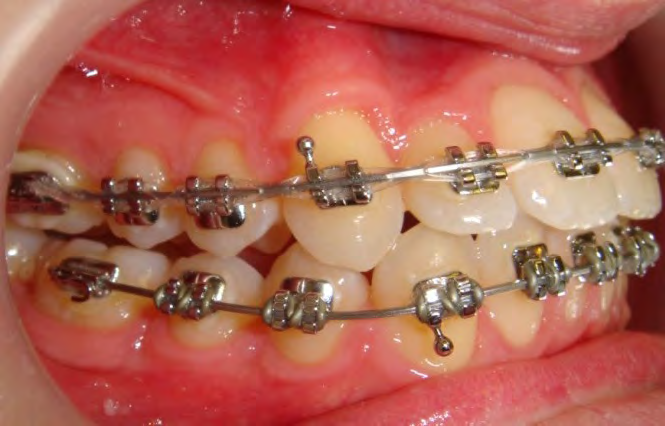

All of the patients below had been told they required extractions by orthodontists, some insisting that they could not be treated without extractions.

They were all treated without extractions, head gear or facemasks at Vakresmil and represent just a small sample of cases treated between 2004–2014.

The patient below had severe crowding of both upper canines and the lower right 5. The upper 4’s and 2’s were actually in contact.